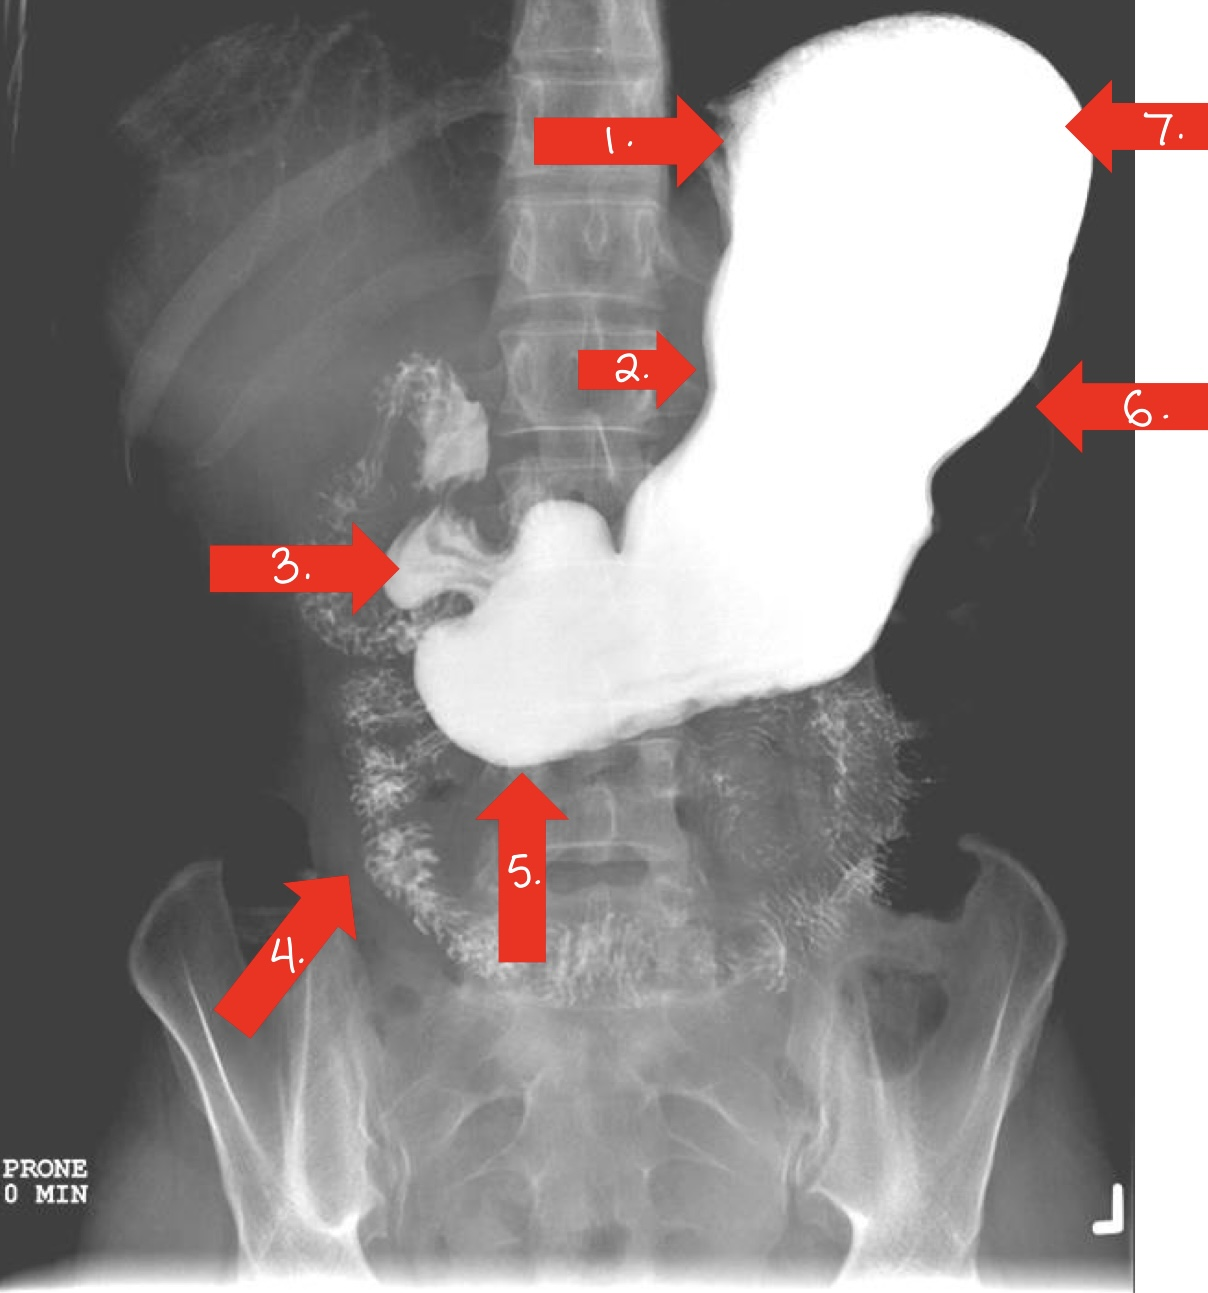

What is 1

gastroesophageal opening

lower esophageal sphincter

sometimes called cardiac antrum/sphincter

What is 2

lesser curvature/stomach

What is 3

doudenal bulb/small intestine

What is 4

jejunum/small intestine

What is 5

pylorus

or pyloric antrum

What is 6

greater curvature/stomach

What is 7

fundus/stomach